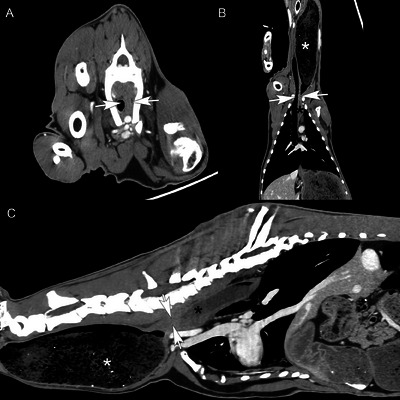

一个4岁的尼日利亚侏儒提出慢性反流和颈部肿胀的三年持续时间。体格检查发现颈部腹侧有一个大肿块。山羊多次尝试吞咽和反刍,但肿块的大小没有明显变化。颈椎x线片显示食道节段性扩张至胸入口水平。CT显示过渡性第七颈椎伴左右肋骨融合,导致食管外压迫和胸入口水平梗阻。这是山羊颈肋引起食管肥大的第一个报告。

A 4-year-old Nigerian Dwarf wether presented for chronic regurgitation and cervical swelling of three years duration. Physical examination revealed a large ventral cervical mass. The goat made repeated attempts to swallow and regurgitate, but the mass did not change significantly in size. Cervical radiographs revealed segmental esophageal dilation to the level of the thoracic inlet. CT revealed a transitional seventh cervical vertebra with fused right and left ribs, resulting in extramural esophageal compression and obstruction at the level of the thoracic inlet. This is the first report of a cervical rib causing megaesophagus in a goat.